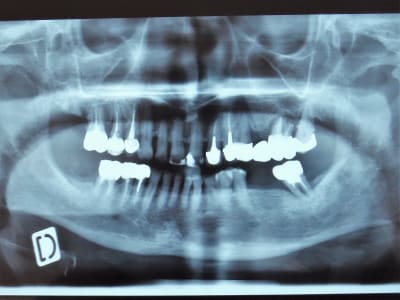

Alors j'ai viré 24, 26 pour 27 on attendrait un peu. Et en secteur 1 la 15, rapport aux images osseuses, et puis c'est toujours bien (mieux) d'avoir 2 édentements encastrés, un de chaque coté, mieux pour les crochets et une dent proth de droite et de gauche cela équilibre bien (putain j'avais un prof macroniste! avec 30 ans d'avance)

La patiente à une patho inflammatoire chronique qui se traite à la cortisone... ostéoporose (médicamenteuse?)... biphosphonates à gogo, les implants on oublie. Déjà pour les exos je serre les fesses.

Revenons à ma patiente, toujours douleur à la pression. "C'est la molaire Docteur" (j'aime bien quand on m’appelle Docteur, au moins le patient est conscient d'où il est et avec qui, "Monsieur", j'ai un doute... ).

Jour de l'exo, Ab Ok (tjrs vérifier chez les vrais malades), et là, il faut en convenir ma patiente ne parle pas la même langue que moi. Oui parce que la molaire... bin c'est la 14, mobilité axiale, sondage positif en dv pour recherche de fracture.

Exo et zolie fêlure de l'apex à la couronne prothétique, c'était bien la peine de ne pas avoir mis d'IC ou de tenon afin de prévenir ce risque :-)))

Je me demande même si un bête screw-post n'aurait pas évité le problème?-(

Je l'ai autopsié, il n'y avait que du composite, de la gutta et du ciment dans la racine.

Tandis que là, c'est indiscutable il y a un inlay-core une CR et une fracture radiculaire... tout est normal. La CR avait plus de 10 ans.

Enfin oui et non, parce que c'est une 27, il n'y a pas de 28, 26, et pas de 38, 37, 36 depuis plus de 10 ans et jamais eu de PAP, la patiente a pris la fuite avant que son ancien CD ne les lui fasse. Il a juste eu le temps de faire les CR et la patiente a pensé que cela faisait beaucoup de ravage pour des PAP qu'elle ne souhaitait pas... c'est comme cela que je l'ai récupéré.